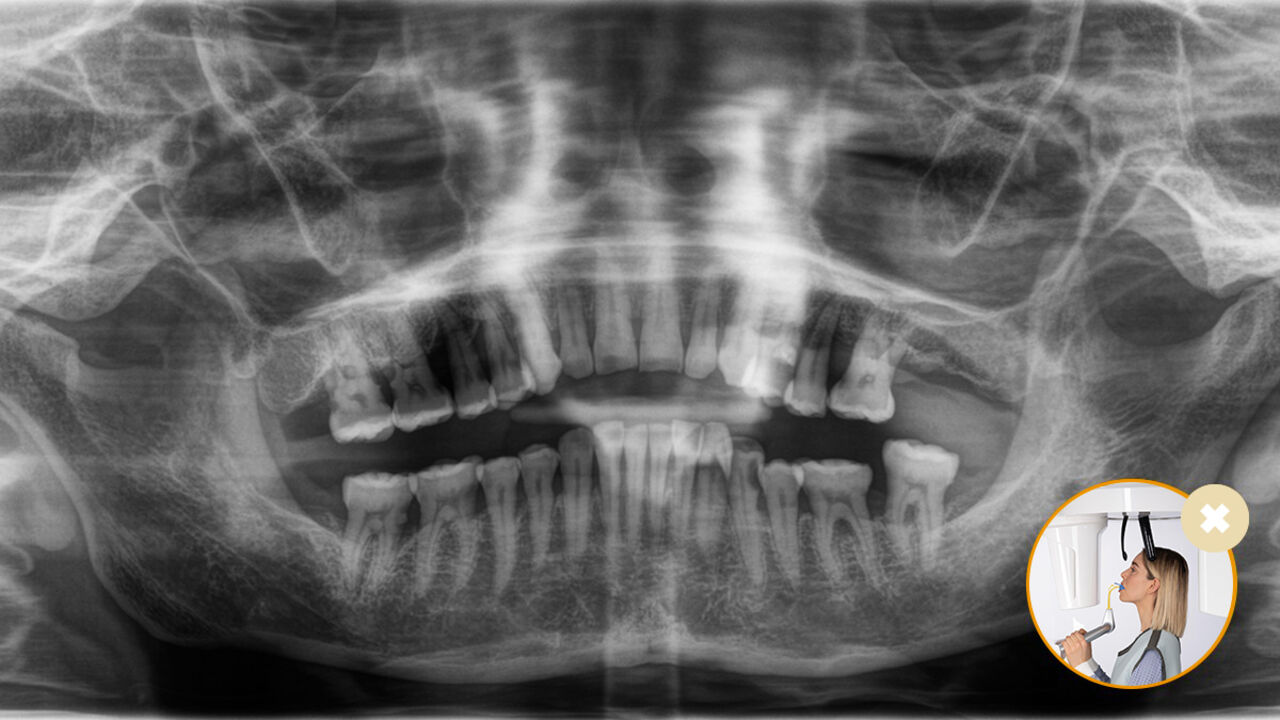

Die korrekte Patientenpositionierung führt zu einer hohen Bildqualität, die eine genaue Diagnose ermöglicht und die Patientenerfahrung erleichtert und verbessert.

Dies ist unser 10-Punkte-Konzept für die einfache Patientenpositionierung und Röntgenbildgebung. Es geht in erster Linie um zwei Dinge: Hochwertige Aufnahme und Komfort für den Patienten und die Assistenten.